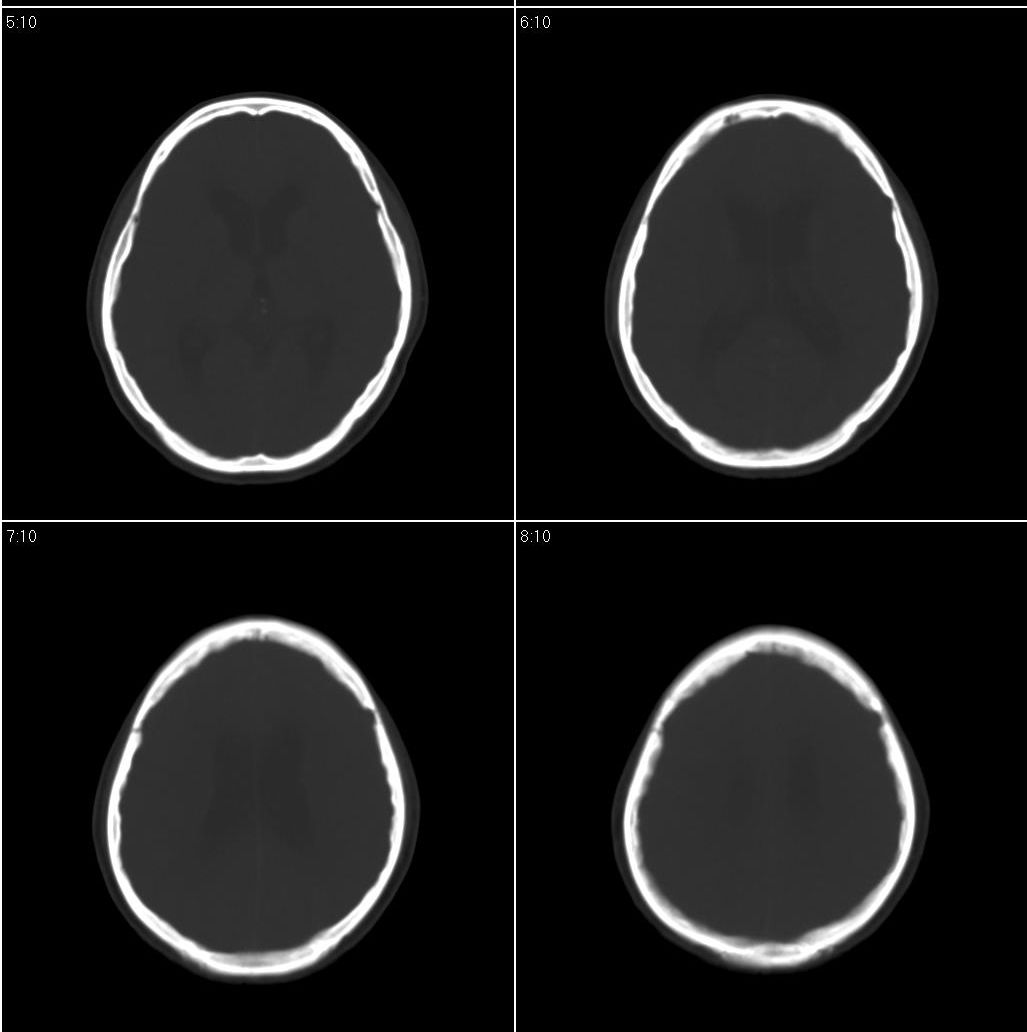

标题: CT16665:男,34岁。近来发现视力不好、眼花。 [打印本页]

标题: CT16665:男,34岁。近来发现视力不好、眼花。

支持右侧小脑半球占位性病变伴梗阻性脑积水。建议增强,上传骨窗,除外听神经瘤

看到骨窗了,右侧内听道扩大(再往下扫一层),支持听神经瘤

现在有骨窗了,内听道口好像被开挖了一样,支持考虑听神经瘤先

右侧桥小脑角区占位性病变,内听道扩大,骨质似见破坏,考虑为听神经瘤

右侧内听道扩大,支持听神经瘤

1)右侧听神经瘤。2)脑积水(梗阻性)。3)空蝶鞍。